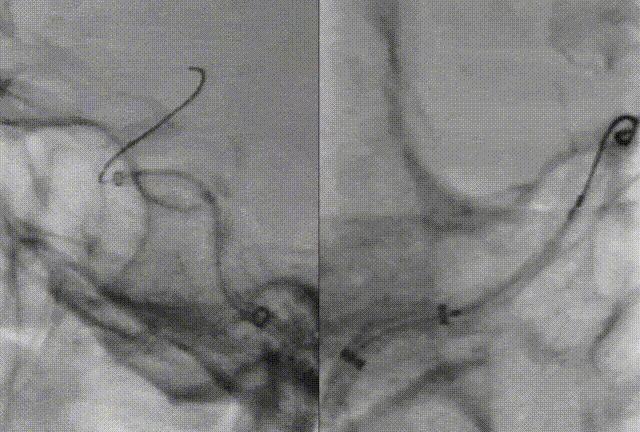

An EDPA-060-190 embolic protection device was introduced via Zenith Distal Access Catheter and positioned in the C2 segment of the ICA. Under fluoroscopy, the filter was seen to open and appose well to the vessel wall. A 7 mm × 50 mm self-expanding stent was deployed at the site of residual stenosis with precise positioning. Post-deployment angiography demonstrated resolution of the dissection and significant improvement of C1 segment stenosis. The protection device was retrieved without visible embolic debris.

Postoperative Angiography

Final angiography in both anteroposterior and lateral projections confirmed restored flow through the right ICA, with good opacification of both the MCA and ACA, without flow limitation.